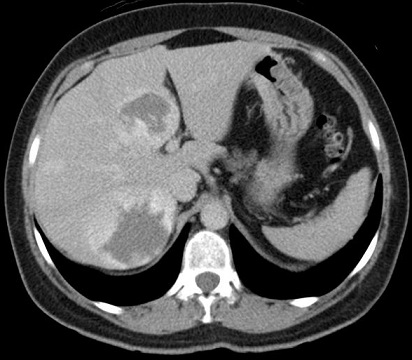

Image TDM de kyste du

foie : Image lesionaire arrondie , de taille variable souvent de

quelque centimetrique . Densite liquidienne de 0

a 15UH

Image radiologique TDM d'une kyste simple

du foie droit en coupe axiale : Aspect

lesionnel a densite variee de 7-15 UH ( hypodense )

avec bord lisse , bien definie et regulier |